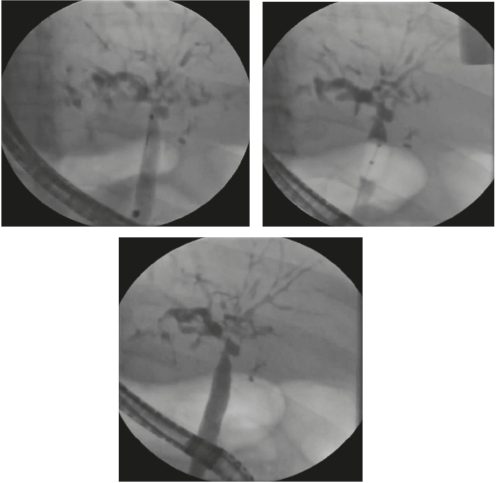

Las guías primarias para la CEP recomiendan la dilatación con balón como tratamiento endoscópico de primera línea (Figura 1). Si se decide realizar cualquier intervención biliar endoscópica se debe estar alerta ante el riesgo de colangitis bacteriana y administrar siempre antibióticos profilácticos de acuerdo con los perfiles de resistencia locales (39). Siempre se debe evaluar la presencia de várices, ya que en los pacientes con la CEP el desarrollo de estas puede darse antes de que sea evidente la cirrosis (7).

Debido a la naturaleza invasiva del procedimiento, entre el 7,3 y el 20 % tienen riesgo de tener complicaciones posendoscópicas, como la pancreatitis, colangitis, perforación de la vía biliar y hemorragia (40).